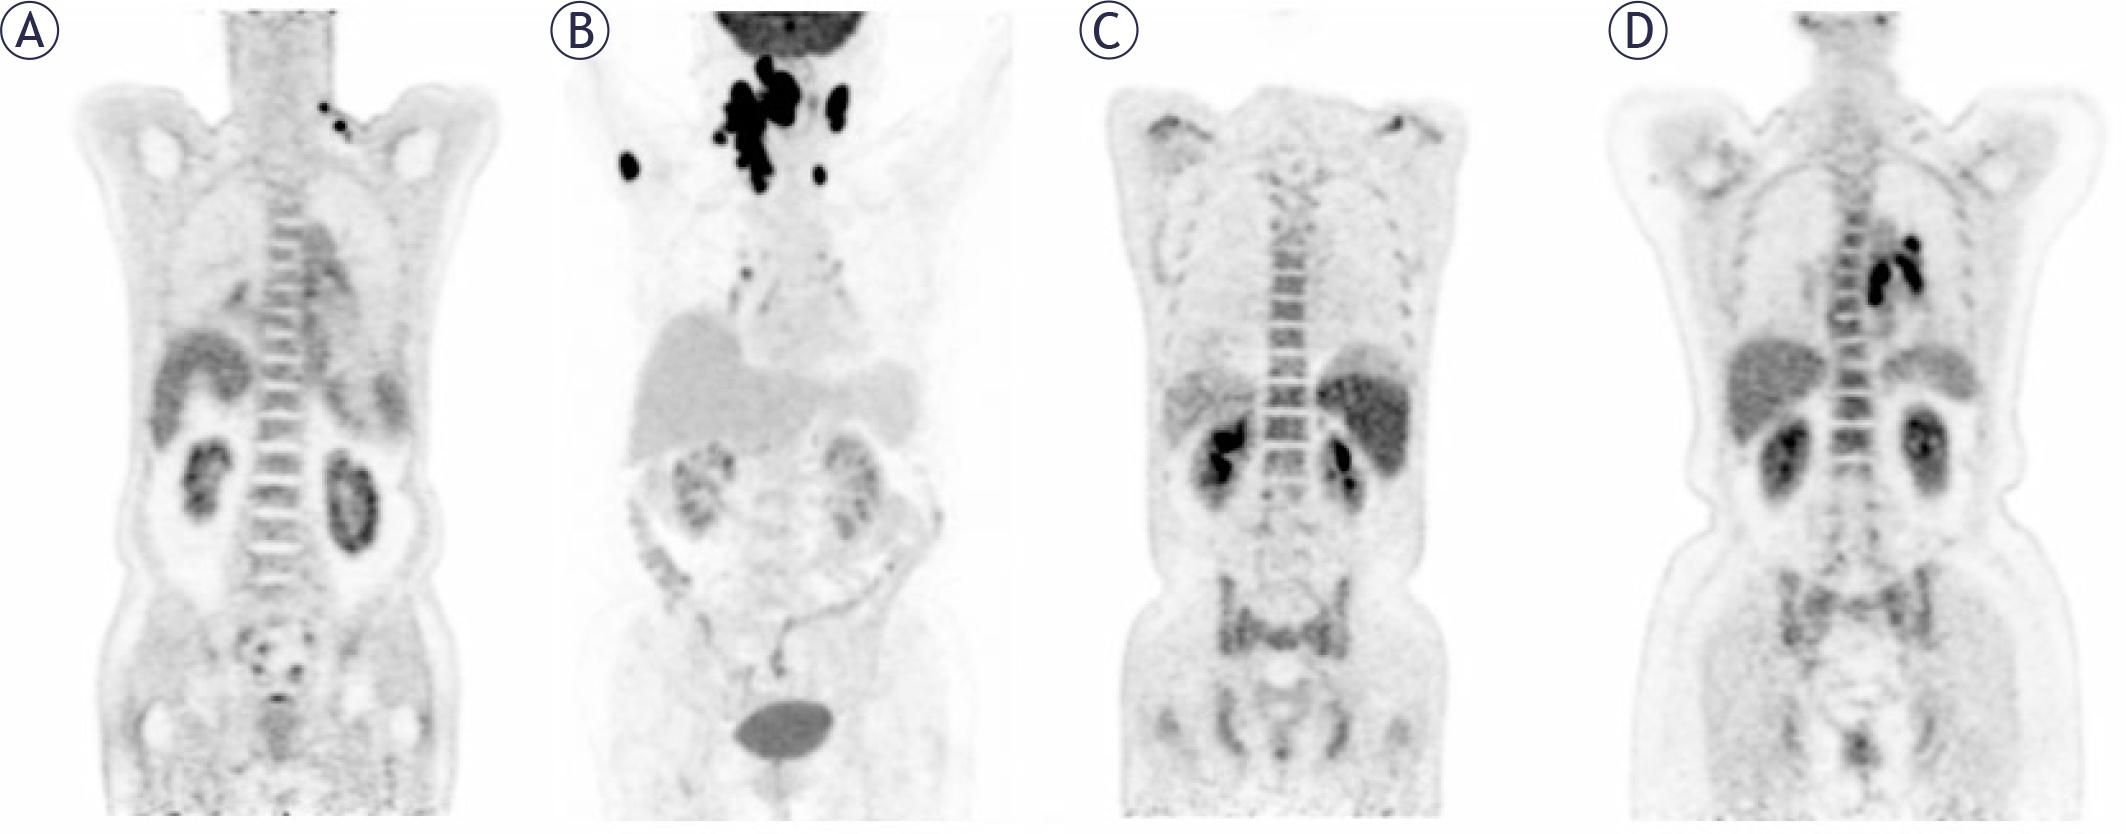

Image interpretation was conducted through visual and semi-quantitative analysis, utilizing glucose activity in the normal liver as a reference to assess the presence of BMI. In cases where BM lesions were identified, they were classified as focal lesions (demonstrating elevated FDG uptake in one or more localized regions) or diffuse lesions (exhibiting a uniform increase in FDG uptake across the entire marrow space). These lesions, with or without associated bone destruction, were distinguished from benign findings based on standard CT images or medical history (e.g., fractures). In such cases, BM positivity on PET/CT was ascertained. The maximum standardized uptake value (SUVmax) of the liver was measured in a 2-cm region of interest in the right lobe, while the highest SUVmax for BM was assessed at lumbar vertebrae 1-5 in cases of diffuse uptake. The BM-to-liver SUVmax ratio (BLR) was calculated to investigate survival outcomes. Two experienced nuclear medicine specialists, each possessing more than 5 years of professional experience, independently interpreted the images, with discrepancies resolved by consensus (Figure 1).

The initial PET maximum-intensity projection images, and lymph nodes pathology confirmed DLBCL with normal (A), focal increased in the right humerus (B), diffuse increased (C, D).